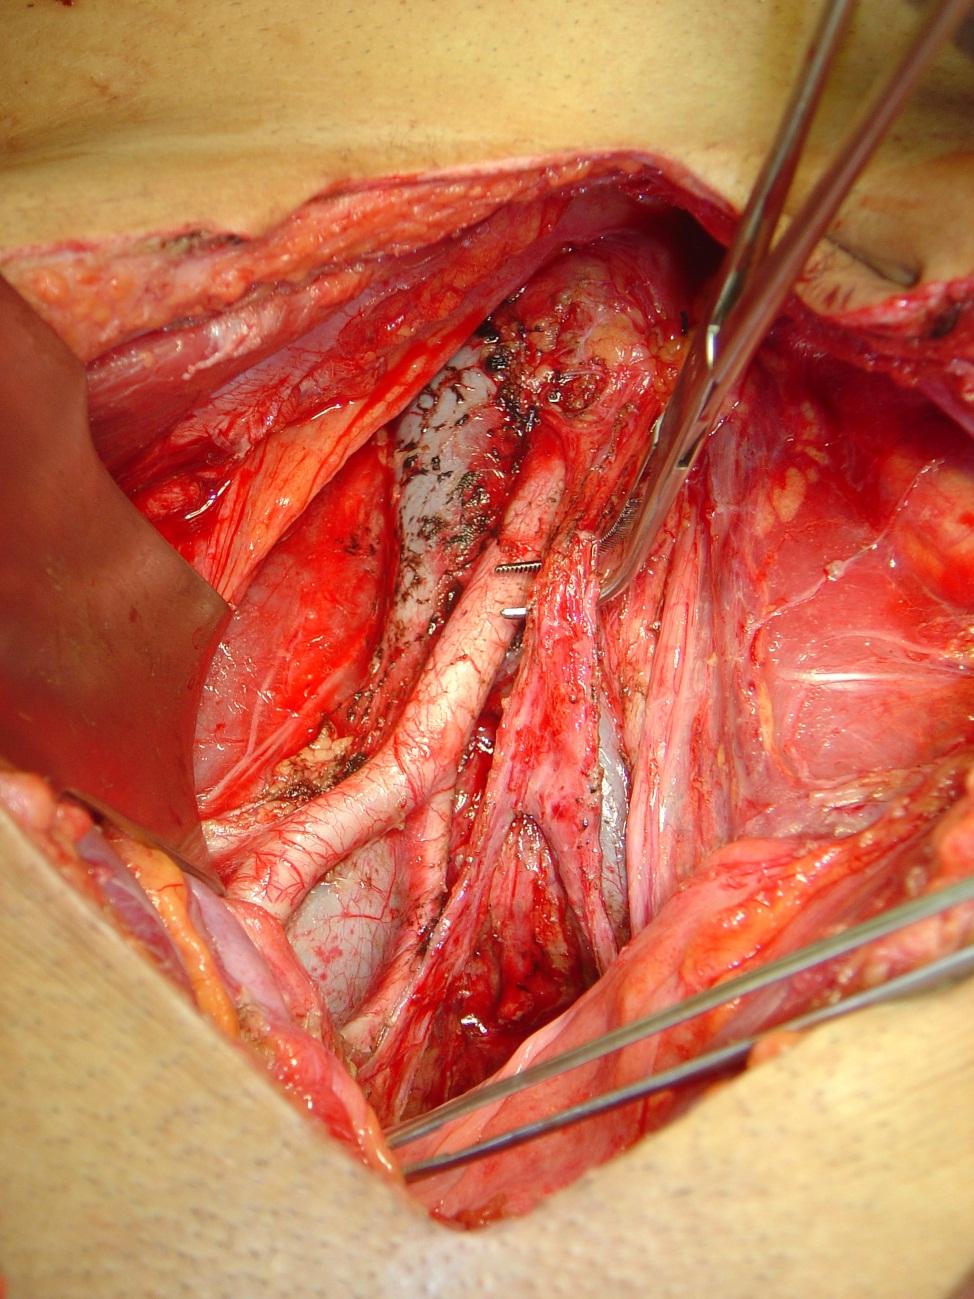

Aspecto da pelve, do mesmo paciente, após retirada dor linfonodos do retroperitônio e da pelve, com preservação de nervos pélvicos. (associado à fotografia abaixo)

Foto: cirurgia realizado pelo Dr. Claudio Quadros.